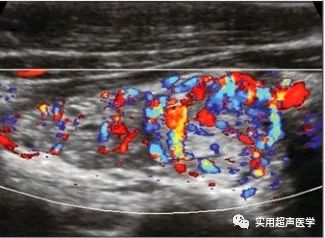

桥本甲状腺炎增生结节为甲状腺纤维化、实质增生所形成,增生结节弥散分布,而癌结节为实质内占位性病变,较孤立,超声检查时结合癌结节内粗大钙化灶或点状钙化及血流分布特点,对伴有癌灶鉴别有一定帮助,彩色多普勒超声可以显示出甲状腺结节内部的血流情况,但由于甲状腺本身血流非常丰富,利用超声图像很难判断其周围血管是否属于新生的。

患者,男,40岁,患有弥漫性桥本甲状腺炎和结节性桥本甲状腺炎(FNA)。左侧叶显示高回声结节(光标)伴低回声晕。彩色多普勒显示结节为血管增生伴中央和外周血流。